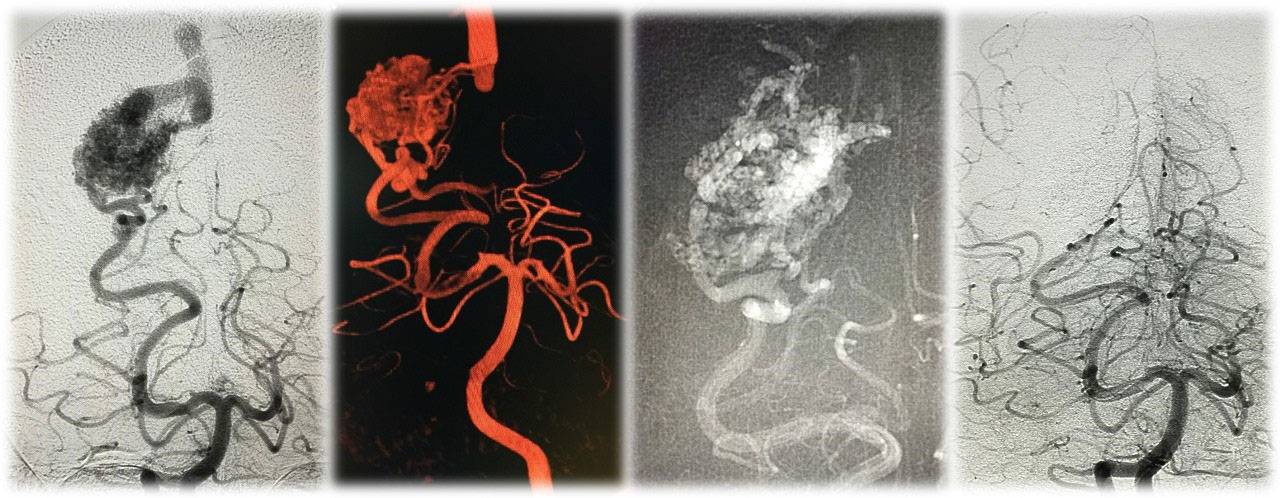

A 5-year-old male child presented with complaints of recurrent generalized tonic–clonic seizures and right-sided weakness ,predominantly involving the lower limb along with anger outbursts and abnormal behaviour.